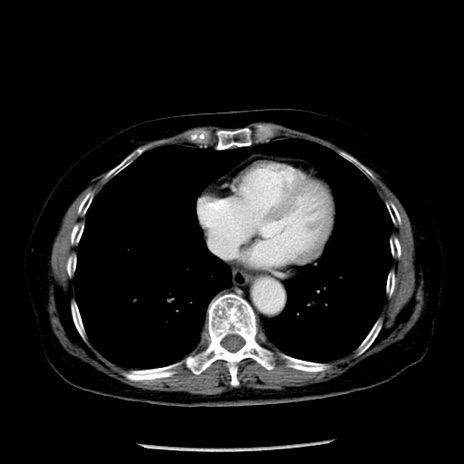

症例13(横断像)

【症例】70歳代女性

【主訴】腹痛、嘔吐

【現病歴】15時間程前(昨晩)より腹痛あり。今朝になっても症状の改善なく、嘔吐あり。腹痛も増悪あり、救急外来受診。

【既往歴】子宮癌全摘術後

【身体所見】意識清明、BP 121/72mmHg、P 74bpm、SpO2 100%(RA)、腹部:平坦・軟、腸雑音ほぼ聴取せず。下腹部・心窩部・臍左上に圧痛あり。反跳痛なし。

【データ】WBC 10600、CRP 0.15